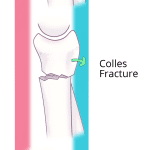

- Colles fracture (Frykman IV)

- Colles fracture – a transverse fracture with dorsal tilt of the distal radial articular surface. May have associated impaction and/or intraarticular extension

- Colles fracture – a transverse fracture with dorsal tilt of the distal radial articular surface. May have associated impaction and/or intraarticular extension